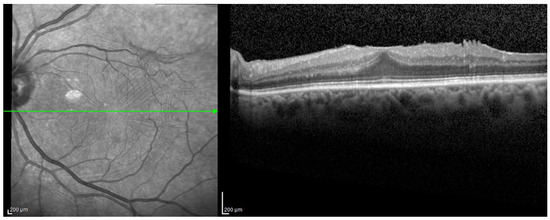

2.2. OCT Grading and Structural Assessment

3.2. Comparison between Structural Parameters in Different Stages of ERM